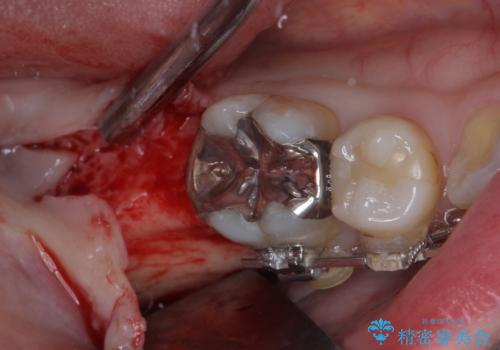

- 口元の突出感と奥歯の欠損を気にして来院された患者様です。

口元の突出感改善には、上下左右の第一小臼歯4本を抜歯し、奥歯の欠損部には矯正治療の途中でインプランを埋入していくこととしました。

矯正治療の後半にインプラント埋入を行うことで、トータルの治療期間を短縮することができました。